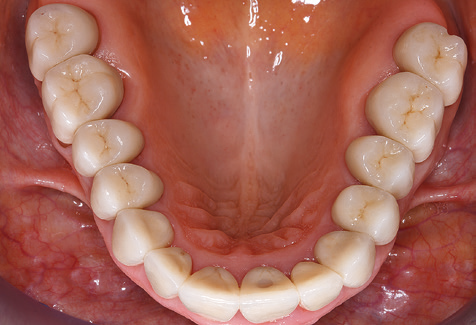

Fig. 9: Le superfici accessibili di impianti e denti sono lucidate con coppette da lucidatura e composti lucidanti adatti. - Fig. 10: Rispettare le istruzioni d'uso di ausili adeguati per l'igiene orale a casa dovrebbe far parte di SPT. - Fig. 11a eb: Situazione clinica 12 anni dopo l'inserimento del restauro protesico. Durante questo periodo, sono state osservate solo la rottura della ceramica del rivestimento estetico sul dente 47 e la necessità di un trattamento endodontico del dente 12. Tutti i restauri funzionano ancora come previsto.

Un'assistenza standardizzata e regolare a misura di rischio nell'ambito di SPT è la chiave per il successo del trattamento clinico a lungo termine nei pazienti con situazione periodontale compromessa. Ciò è particolarmente vero per i pazienti a cui vengono applicati impianti dopo il trattamento parodontale completato con successo (Fig. 11a e b).